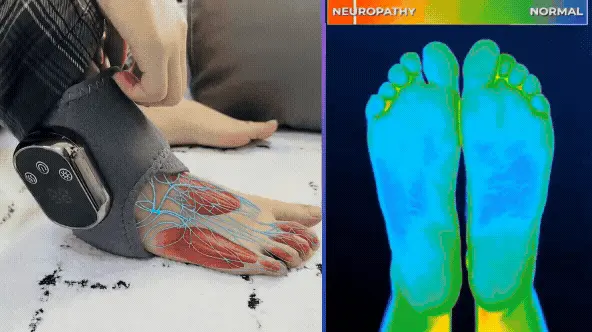

Eliminate foot pain, burning, and tingling in just 15 minutes a day!

Qinux FootRevita is a simple home-use massager that employs the innovative Triple Action FootTherapy™ technology to address the root cause of foot pain, burning, and tingling.

No drugs or side effects!